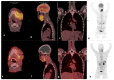

Materials and methods: In this prospective cross-sectional study, twenty-three (23) patients aged 52.9 ± 10.4 (19.6), 17 males and 6 females with primarily diagnosed (n = 17) or pre-treated (n = 6) SCC of the oral cavity (OCSCC, n = 11), oropharynx (OPSCC, n = 9), nasopharynx (NPSCC, n = 2) and unknown primary (n = 1) underwent imaging with [68Ga]Ga-Pentixafor-PET/CT. In 16/23 patients 2-[18F]fluoro-2-deoxy-D-glucose ([18F]F-FDG) served as a standard reference. All lesions were visually rated using a 5-point Likert scale. For both tracers, maximum standardized uptake values (SUVmax) and the total lesion uptake (TLU) were recorded and compared using the Wilcox-signed rank test. In addition, the tumor-to-background ratios were derived using the liver (TLR), spleen (TSR), and posterior cervical muscles (TMR) as background. The relationships between the SUVs of the two tracers were assessed using the Spearman correlation. CXCR4 immunohistochemistry (IHC) staining was correlated with 68Ga-Pentixafor-PET/CT in 21/23 patients.

Results: Ninety-one percent (21/23) of tumors were visually detected on [68Ga]Ga-Pentixafor; however, [68Ga]Ga-Pentixafor was less intense compared with [18F]F-FDG-PET. Quantitative analysis showed higher [18F]F-FDG SUVmax in comparison with [68Ga]Ga-Pentixafor (16 ± 6.7 vs. 5.8 ± 2.6 g/mL, p = 0.011) and SUVmean (9.3 ± 4.1 vs. 3± 1.6 g/mL, p < 0.001) and TBR 4.9 ± 2.3 vs. 2.36 ± 1.4 p = 0.014. Nasopharyngeal cancer demonstrated more intense tracer accumulation than oropharyngeal and oral cavity malignancies. CXCR4 IHC staining was positive in 15/21 patients, and there was a statistically significant correlation between IHC staining and [68Ga]Ga-Pentixafor SUVmean r = 0.5 p = 0.027, and performance status r = 0.83 p = 0.0104.

Conclusions: In conclusion, although [68Ga]Ga-Pentixafor cannot replace [18F]F-FDG as a diagnostic tool because of its lower avidity, the correlation between CXCR4 targeted 68Ga-Pentixafor PET imaging and CXCR4 IHC staining indicates the potential of 68Ga-Pentixafor as an effective tool for selecting patients who may benefit from therapies targeting CXCR4. In addition, [68Ga]Ga-Pentixafor has no physiological brown fat uptake, which often obscures cervical lesions on [18F]F-FDG PET/CT imaging.